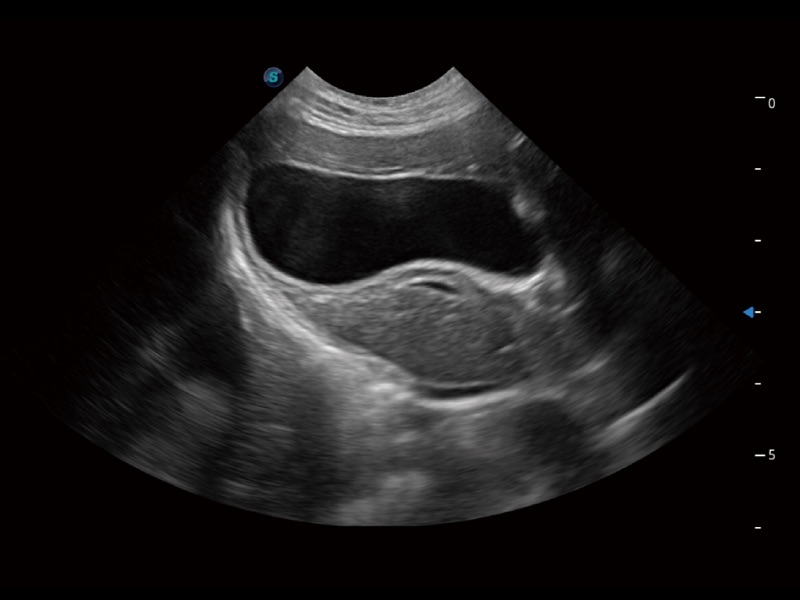

(猫)胆囊

优异的基础图像

ProPet 70 全新的动物超声智能软件和丰富的探头群,为动物医生提供了高清晰度和精细分辨率的图像,无论在宠物、马科、畜牧还是实验室动物等应用中都可以轻松应对,为您的日常工作带来满意的体验。